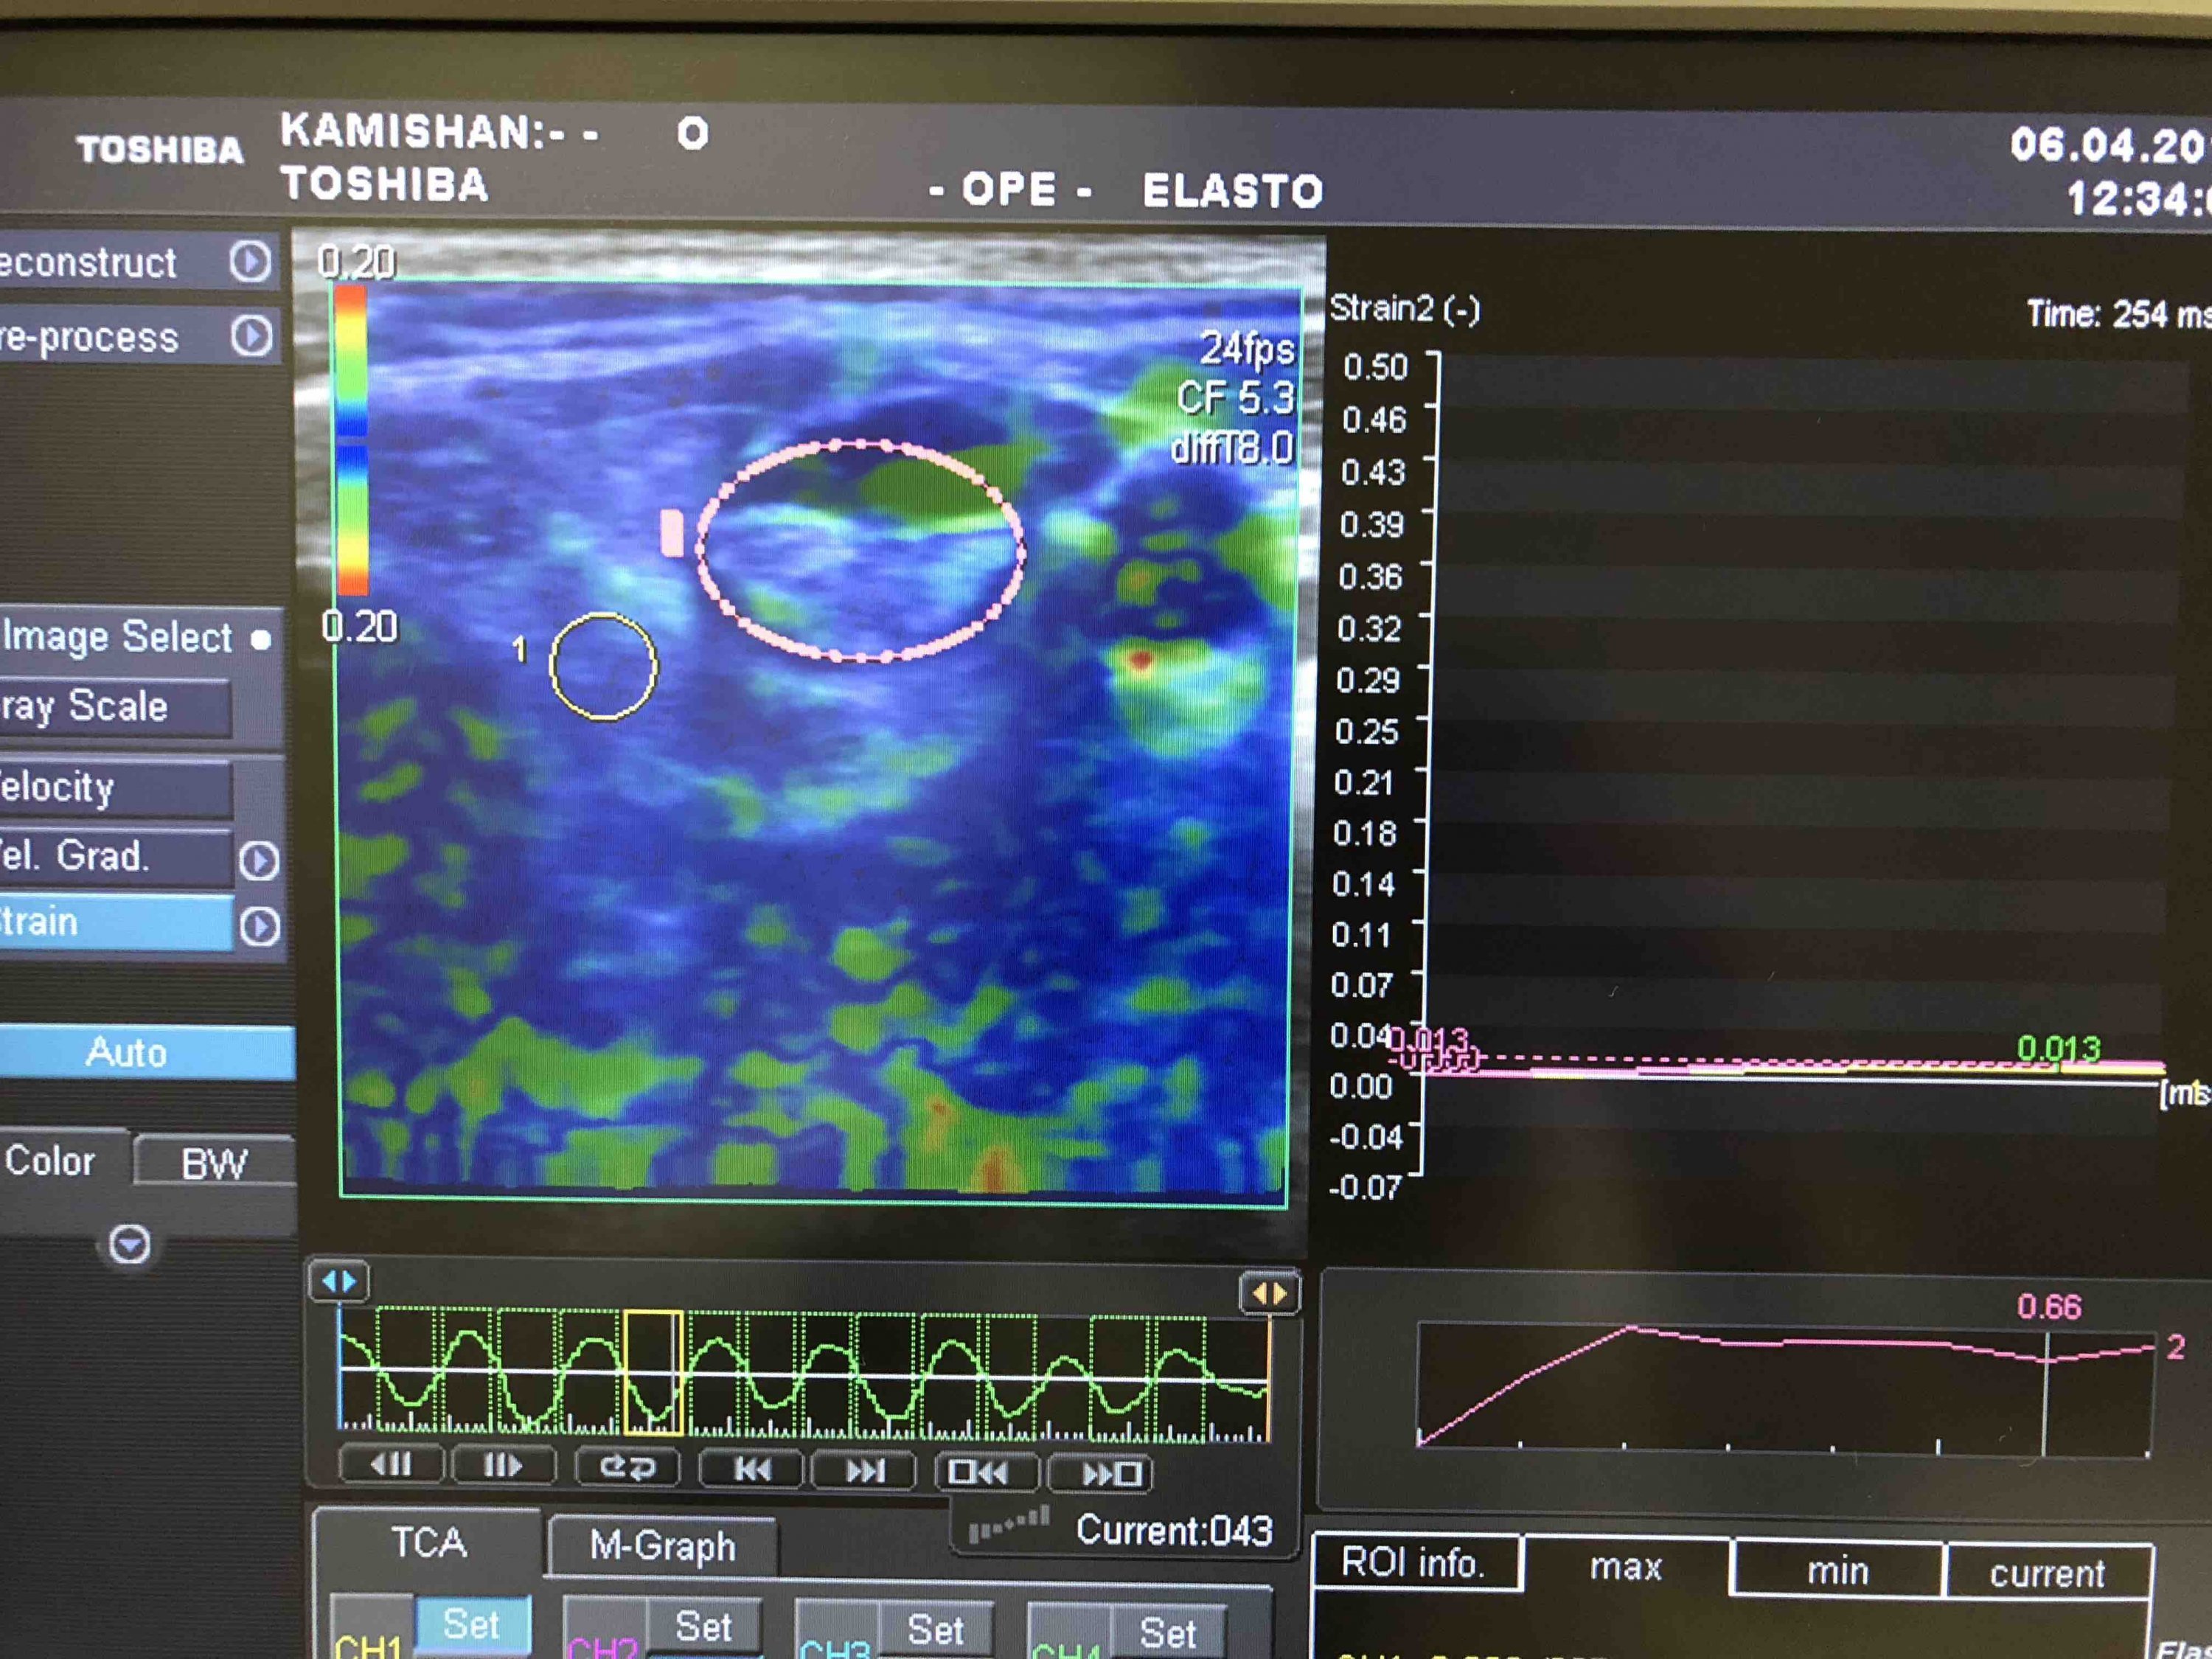

У нашому медичному центрі ви отримаєте консультацію онколога, проведете УЗД органів черевної порожнини, органів малого тазу, молочних залоз, щитоподібної залози, еластографію, УЗД м’яких тканин, простати та ін. Також ми проводимо лабораторні дослідження, зокрема на онкомаркери. У нашому закладі можна отримати таку послугу, як біопсія утворень молочної та щитоподібної залоз, м’яких тканин.